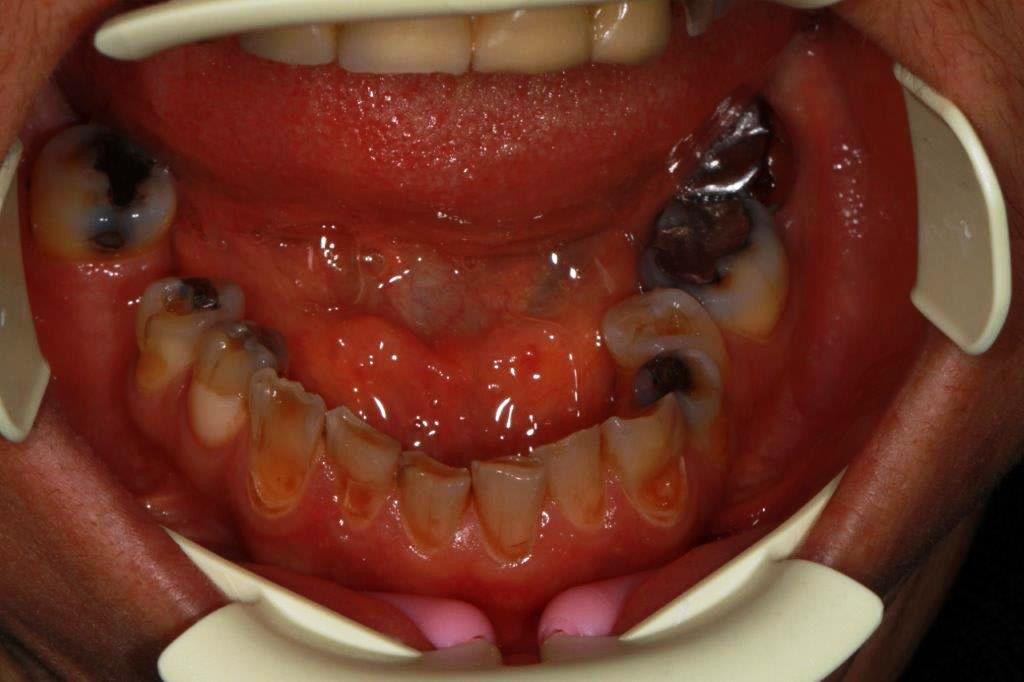

patiente 48 ans ...voudrait pouvoir manger et sourire...

Chouette cas, le plus dur sera évidemment de lever l'articulé croisé.

La DV est-elle conservée? Ce sera plus simple si il faut la remonter.

Non je ne croyais pas que ce cas se ferait, et la patiente vient de decider...donc empreintes et réflexions.

Devis accepté acompte versé il me reste a trouver la solution.

À priori travail sur dents vivantes sauf celles qui sont. Déjà traitées dv légèrement modifiée,et retablir une occlusion standard...un peu chaud quand même.

Pas d'implant prévu ni ortho

On va faire chauffer l'Emax....

Pff, un disjoncteur à 6 ans aurait évité tellement d'emmerdes.